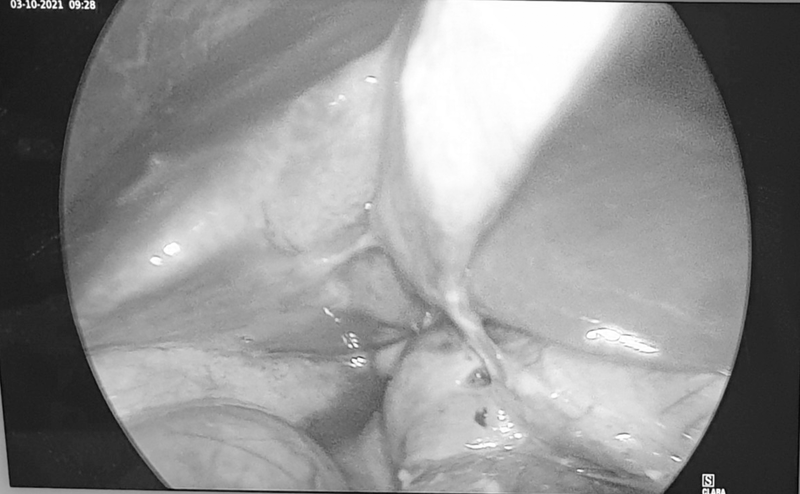

| Hình ảnh lỗ thủng hành tá tràng qua nội soi của bệnh nhân (Ảnh - BSCC) |

Ngay lập tức, bệnh nhân được chuyển mổ cấp cứu. Các bác sĩ đã phẫu thuật nội soi thám sát ổ bụng của bệnh nhân và phát hiện 1 lỗ thủng khoảng 0.3cm vùng hành tá tràng, ổ loét non mềm mại, nhiều dịch ổ bụng. Bệnh nhân được khâu lỗ thủng qua nội soi, bơm rửa ổ bụng, đặt dẫn lưu ổ bụng, dùng thuốc kháng sinh sau mổ, thuốc giảm tiết dịch vị dạ dày.